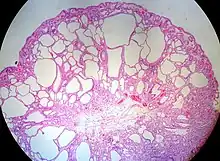

Fundic gland polyp Fundus of stomach Cystically dilated glands lined by chief cells, parietal cells and mucinous foveolar cells.[5] Very low or none, when sporadic.[6]

Fundic gland polyposis